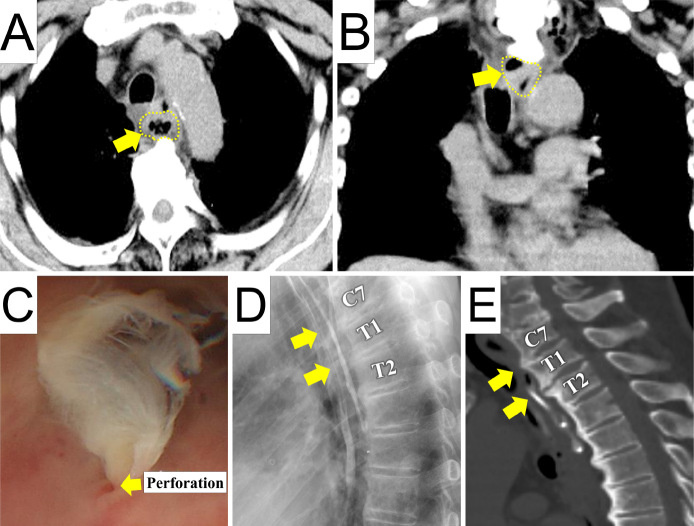

Intramedullary Spinal Cord Abscess due to Traumatic Esophageal Perforation Associated with Cervicothoracic Anterior Osteophytes: A Case Report.